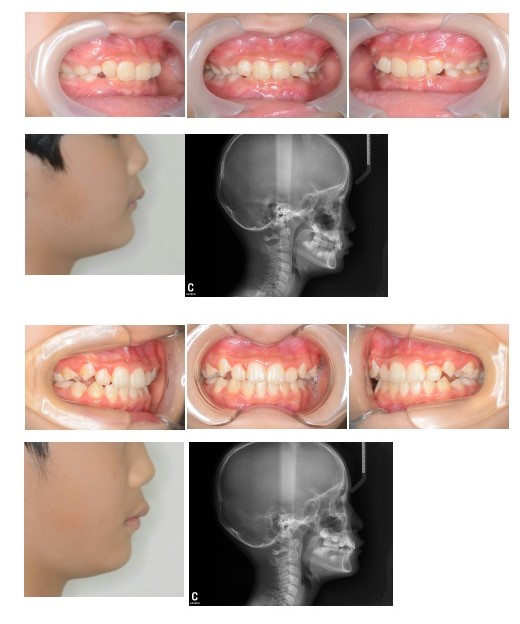

いびきの原因はさまざまですが(鼻疾患、扁桃肥大、アデノイド増殖、肥満など)、歯並びを治すことによって、いびきが改善することがあります。

前歯のかみ合わせが深い場合、下あごの前方への成長が阻害されます。

前歯のかみ合わせを浅くして、下あごの成長を前方に促進することによって、気道が広がりいびきも改善することがあります。

レントゲン上で気道が広がっているのが確認できます。

主訴:かみ合わせが深い、いびき

診断名:過蓋咬合

年齢: 9歳

装置名:可撤式筋機能訓練装置

治療費(施術料 装置料 調整料): 28万(税込み)

永久歯交換後は細かい歯並びを治すには要望に応じてU期治療を行います。。

治療期間:1年

考えられるリスク:歯肉退縮 口内炎